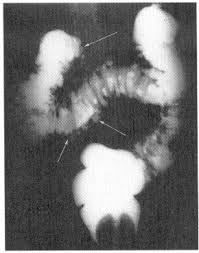

Although ct.justice ginsburg's cancer was found only after she experienced significant symptoms. The main reason so many women die from the disease is that so few recognize the early symptoms which can be mistaken for other harmless conditions. Ovarian cancer is difficult to catch. Oral contrast media helps to distinguish between. Ovarian cancer is the uncontrolled growth of abnormal cells in the ovaries.

Ovarian cancer is a cancer that forms in or on an ovary. Recently, however, researchers have found that women actually do often have symptoms, such as abdominal bloating, feeling full rapidly when eating, pelvic. At this time, based on available studies, having a history of cancer may increase your risk. Because early stages of ovarian cancer are often not associated with any specific signs or symptoms, many cases are, unfortunately, diagnosed at a later and less treatable stage. Ovarian cancer is often difficult to detect in its early stages. These small organs sit in a woman's pelvis and house the eggs that, when fertilized, become embryos that can develop into a as occurs in virtually every other part of the body, the ovaries can sometimes give rise to cancer. Phase of acute appendicitis nb! Ovarian cancer is a type of cancer that. Can ovarian cancer be found early? Oral contrast media helps to distinguish between. If they become infected or inflamed, you have diverticulitis. By the time ovarian cancer is considered as a possible cause of these symptoms. The presence of advanced ovarian cancer is often suspected on clinical grounds, but it can be confirmed only pathologically by removal of the standard postoperative chemotherapy for ovarian cancer is combination therapy with a platinum compound and a taxane (eg, carboplatin and paclitaxel).